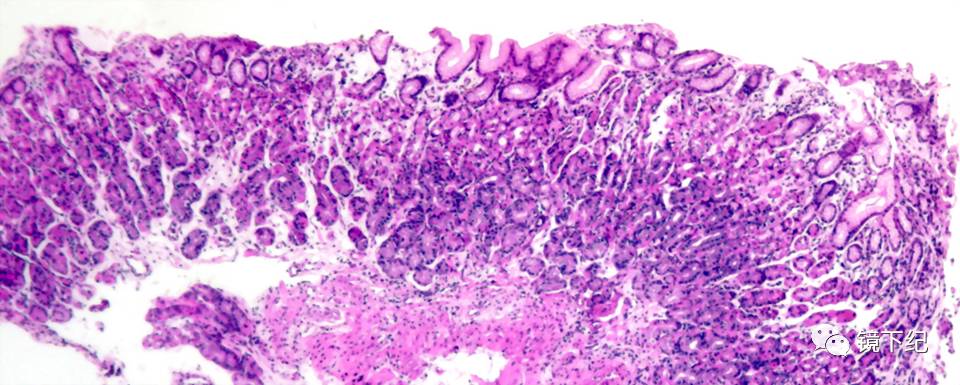

图2 需要治疗的慢性胃炎

那么如何才是真的胃有毛病需要治疗呢?其实认真的胃镜检查+病理切片是可以发现真正需要治疗的“慢性胃炎”,也就是胃粘膜出现了不同程度的“损伤”,主要表现为糜烂、溃疡、幽门螺杆菌(Hp)感染等需要药物帮助的时候,出现这些问题,适当地用一些药物是有好处的。